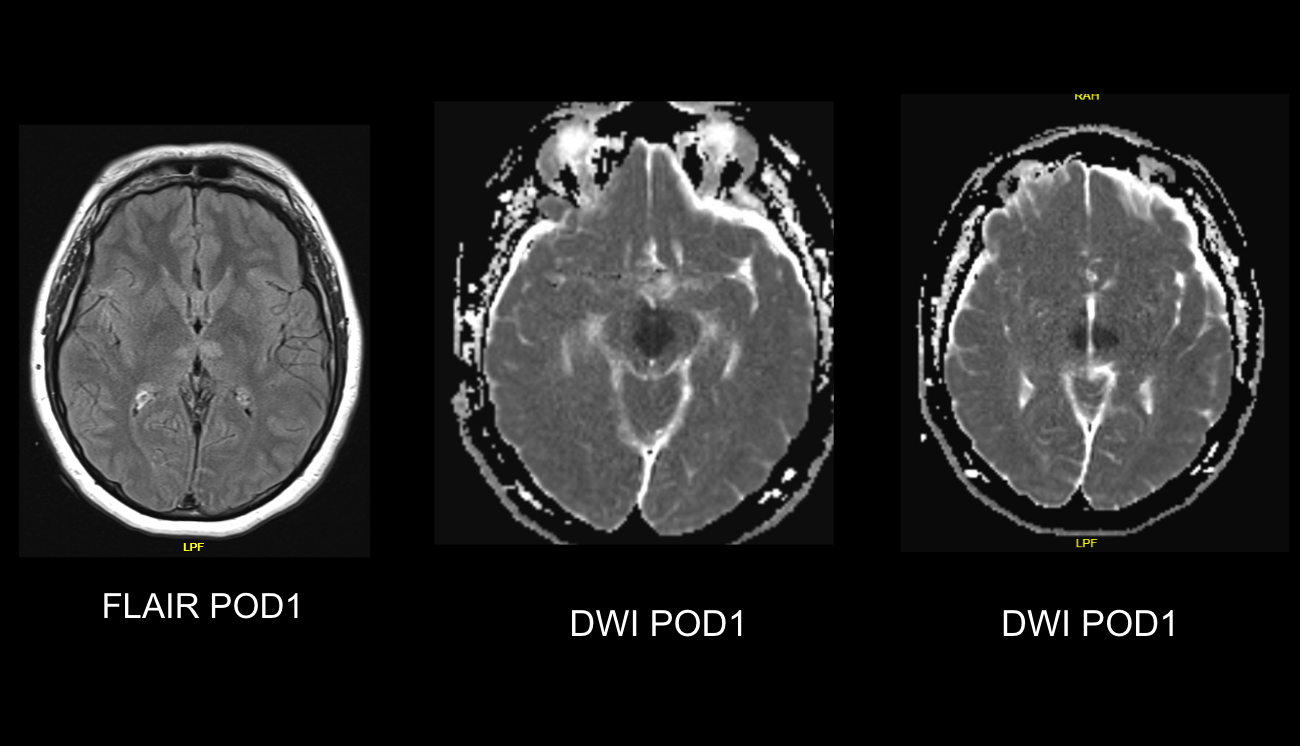

Hyperglycemia presenting with visual hallucinations due to occipital lobe seizures

Hoe Chin Chua

Hui Jin Chiew

Zigui Lim

Wijesoma Nadika

Lin Wah Goh

Background:

Hyperosmotic hyperglycemic nonketotic state (HHS) is associated with myriad neurological complications such as seizures.

Methods:

We report a case presenting with visual hallucinations due to occipital lobe epilepsy.

Results:

A 67-year old woman with chronic hypertension, hyperlipidemia and diabetes mellitus non-compliant to medication presented with a 10-day history of recurrent visual phenomena in the left visual field. She described stationery multi-coloured flashing lights which decreased in intensity, brightness and size after 3 minutes. She was alert and conscious during attacks. There was no limb jerking. Neurological examination was normal with no visual field defect. Capillary glucose was 28.1 mmol/L, Hba1c 9% and B-hydroxybutyrate < 0.1. She was treated with actrapid 8 units, glipizide 5 mg BD and empagliflozin 12.5 mg OM. Interictal electroencephalogram was normal with no epileptiform activity. Brain magnetic resonance imaging revealed restricted diffusion in the right occipital cortex with corresponding cortical thickening and increased FLAIR signal with subtle hypodensity on GRE sequence. Her visual symptoms improved dramatically with hydration and diabetic control. She was treated with a short course of keppra. One month later repeat MRI brain showed resolution of the DWI and FLAIR abnormalities.

Conclusions:

Visual hallucinations are an uncommon but well recognised and fully reversible complication of HHS. Clinicians should not forget HHS in the workup of occipital lobe.

Initial dwi

D